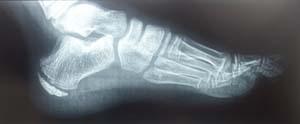

In radiografia, si nota come vi sia un distacco della porzione posteriore del calcagno dal resto dell'osso. Ciò è tipico del MS.